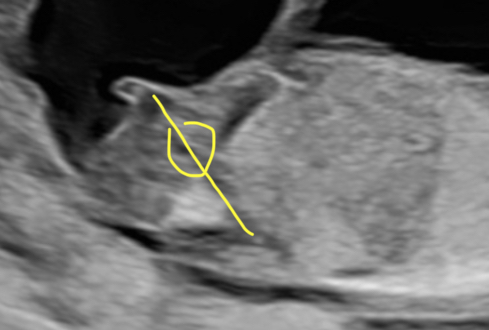

@Carii Ich meinte, dass das von mir gelb markierte vermutlich der NUB ist 😅 Also direkt der weiße, etwas dickere Strich in der Mitte der gelben Markierung. Würde mich freuen, wenn du es dann auflöst oder noch jemand anderer seine Meinung dazu abgeben will ☺️

@Carii Ich tue mir bissi schwer, den Nub ausfindig zu machen. Wenn’s aber das ist was ich vermute, dann würde ich auf Mädchen tippen 😊 Hast du noch weitere Bilder? Die Perspektive passt aber gut für den Nub ;-)

@Carii ist zu früh, um die Zeit haben beide Geschlechter noch ein Zipfelchen abstehen. Demnächst könnte man dann die Nub-Theorie anwenden aber dazu braucht man ein schönes Foto von der Seite des Babys (gerne googlen).